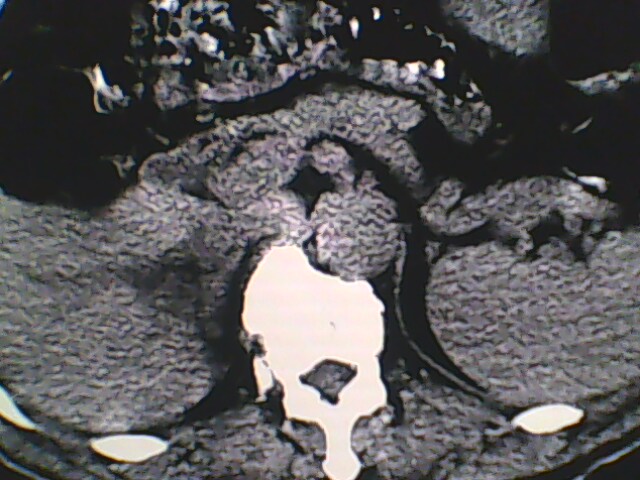

男,56岁,高血压,临床怀疑肾上腺问题,肝脏怎么那么高啊?能描述一下么?

右侧膈膨升,间位结肠,胸腰椎退行性骨关节病,右侧肾上腺可疑增生(图像颗粒太粗,窗太窄,不好看)。

支持 右侧膈膨升,间位结肠;胸腰椎退行性骨关节病;双侧肾上腺可疑增生。

楼主医院的ct机该换了。